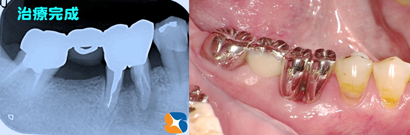

ブリッジ

コラム「ブリッジ」の画像